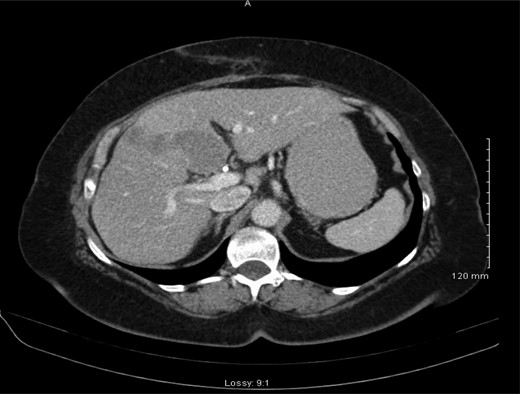

Histology demonstrated a 2.5 cm opaque stone and small cell undifferentiated carcinoma with tumour present in all layers of the gallbladder and lympho-vascular structures with invasion into the liver parenchyma. A subsequent staging computerized tomographic (CT) thorax, abdomen and pelvis demonstrated involvement of the lymph nodes within the coeliac axis and the porta hepatis, 3 mm nodular density in the right upper lobe of the lung and evidence of a metastatic deposit in the medial segment of the left hepatic lobe (Fig. 2). However, her completion staging CT brain revealed normal appearance.

Abdominal CT scan demonstrating metastasis to medial segment of left hepatic lobe.

Following review of the case at a multi-disciplinary meeting, the patient was referred to oncology. A consultation was also sought from hepatobiliary which indicates that she is extremely unlikely to benefit from any liver resection as the disease has progressed far to the lung and systemic lymph nodes, however, chemotherapy and a follow-up CT were suggested. She had three cycles of chemotherapy with Cisplatin and Etoposide, and a follow-up staging CT scan demonstrated progression of the disease, predominantly in the liver with new five lesions (Fig. 3), therefore, Cisplatin and Etoposide were stopped and she was switched to second line chemotherapy in form of FOLFIRI 20% dose reduction.

Re-staging abdominal CT scan demonstrating progression of the disease.